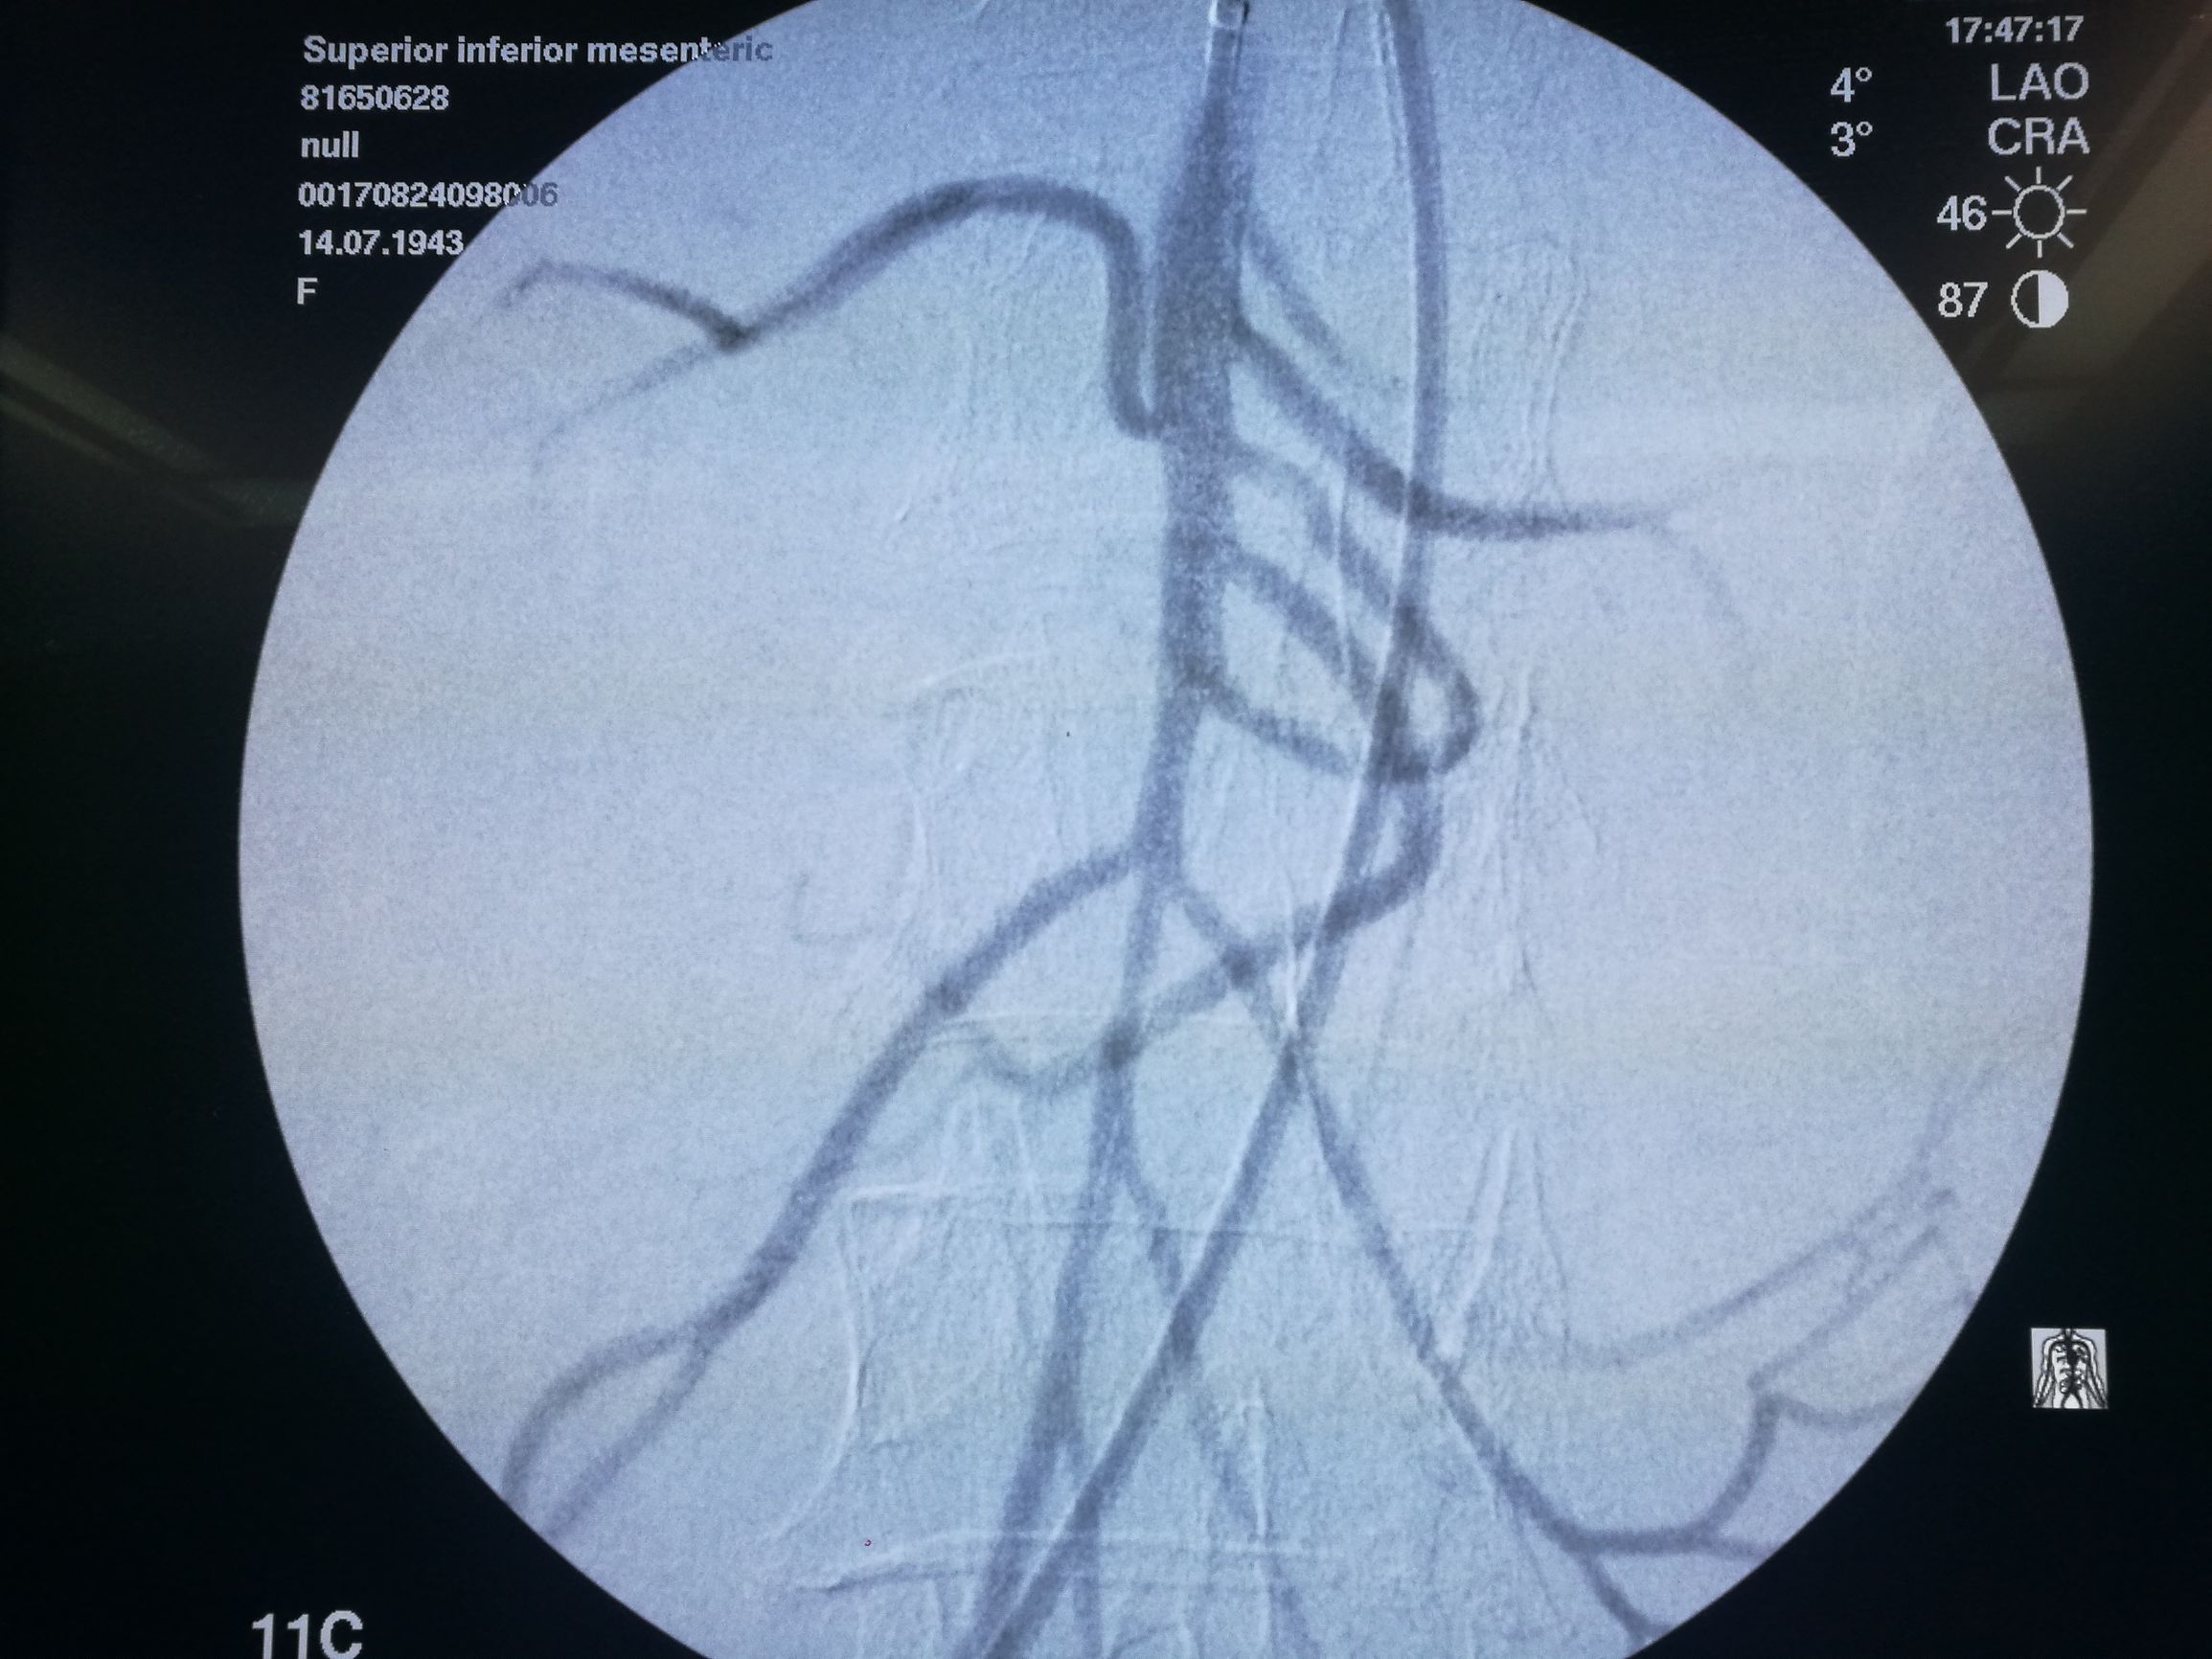

以EV3 SPIDER保护伞取栓(图4)配合6F 指引导管抽吸,取出较多血栓,造影肠系膜上动脉血流通畅

图4. 以Spider保护伞取栓